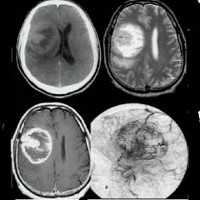

Опухоль головного мозга — глиобластома. Компьютерная томография (КТ). Синяя звездочка в центре обозначает зону центрального некроза опухоли, заполненную жидкостью. Желтые стрелки — окружающий мягкотканный компонент опухоли. Красные звездочки — перифокальный отек мозга. Наблюдается смещение срединных структур и угроза нисходящего транстенториального вклинения мозга.

Проявления опухоли на КТ-сканах без контрастного усиления включают неоднородное образование с нечеткими краями; внутренние области низкой или жидкостной плотности являются очагами некроза (представлены более, чем в 95% МФГ); внутренние области высокой плотности, являющиеся очагами геморрагии или, реже, кальцификациями (они более характерны в тех случаях, когда МФГ является результатом трансформации из астроцитомы низкой степени злокачественности); и значительный масс-эффект и отек (возогенная природа отека).

Исследование КТ с контрастным усилением значительно увеличивает выявление таких признаков, как неровные контуры образрвания, неоднородность, возможное кольцевидное контрастное усиление в периферических отделах патологической зоны.